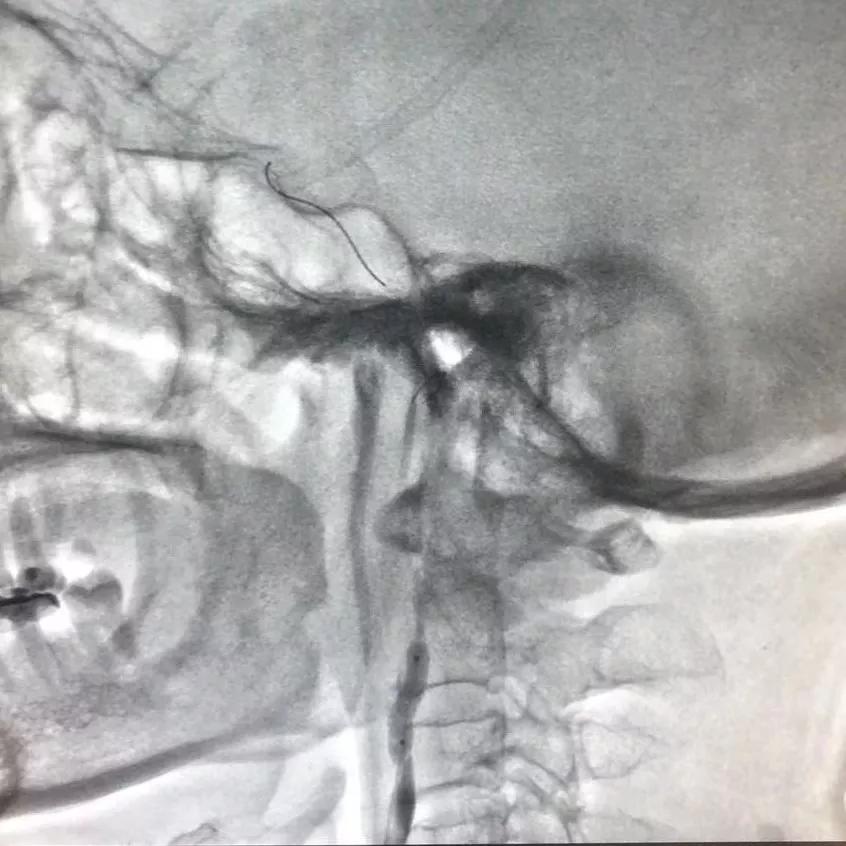

支架展开,造影图示狭窄消失

术后蒙片支架打开良好

造影图提示:支架位置佳,膨胀好,未见内漏,原狭窄段基本恢复正常。